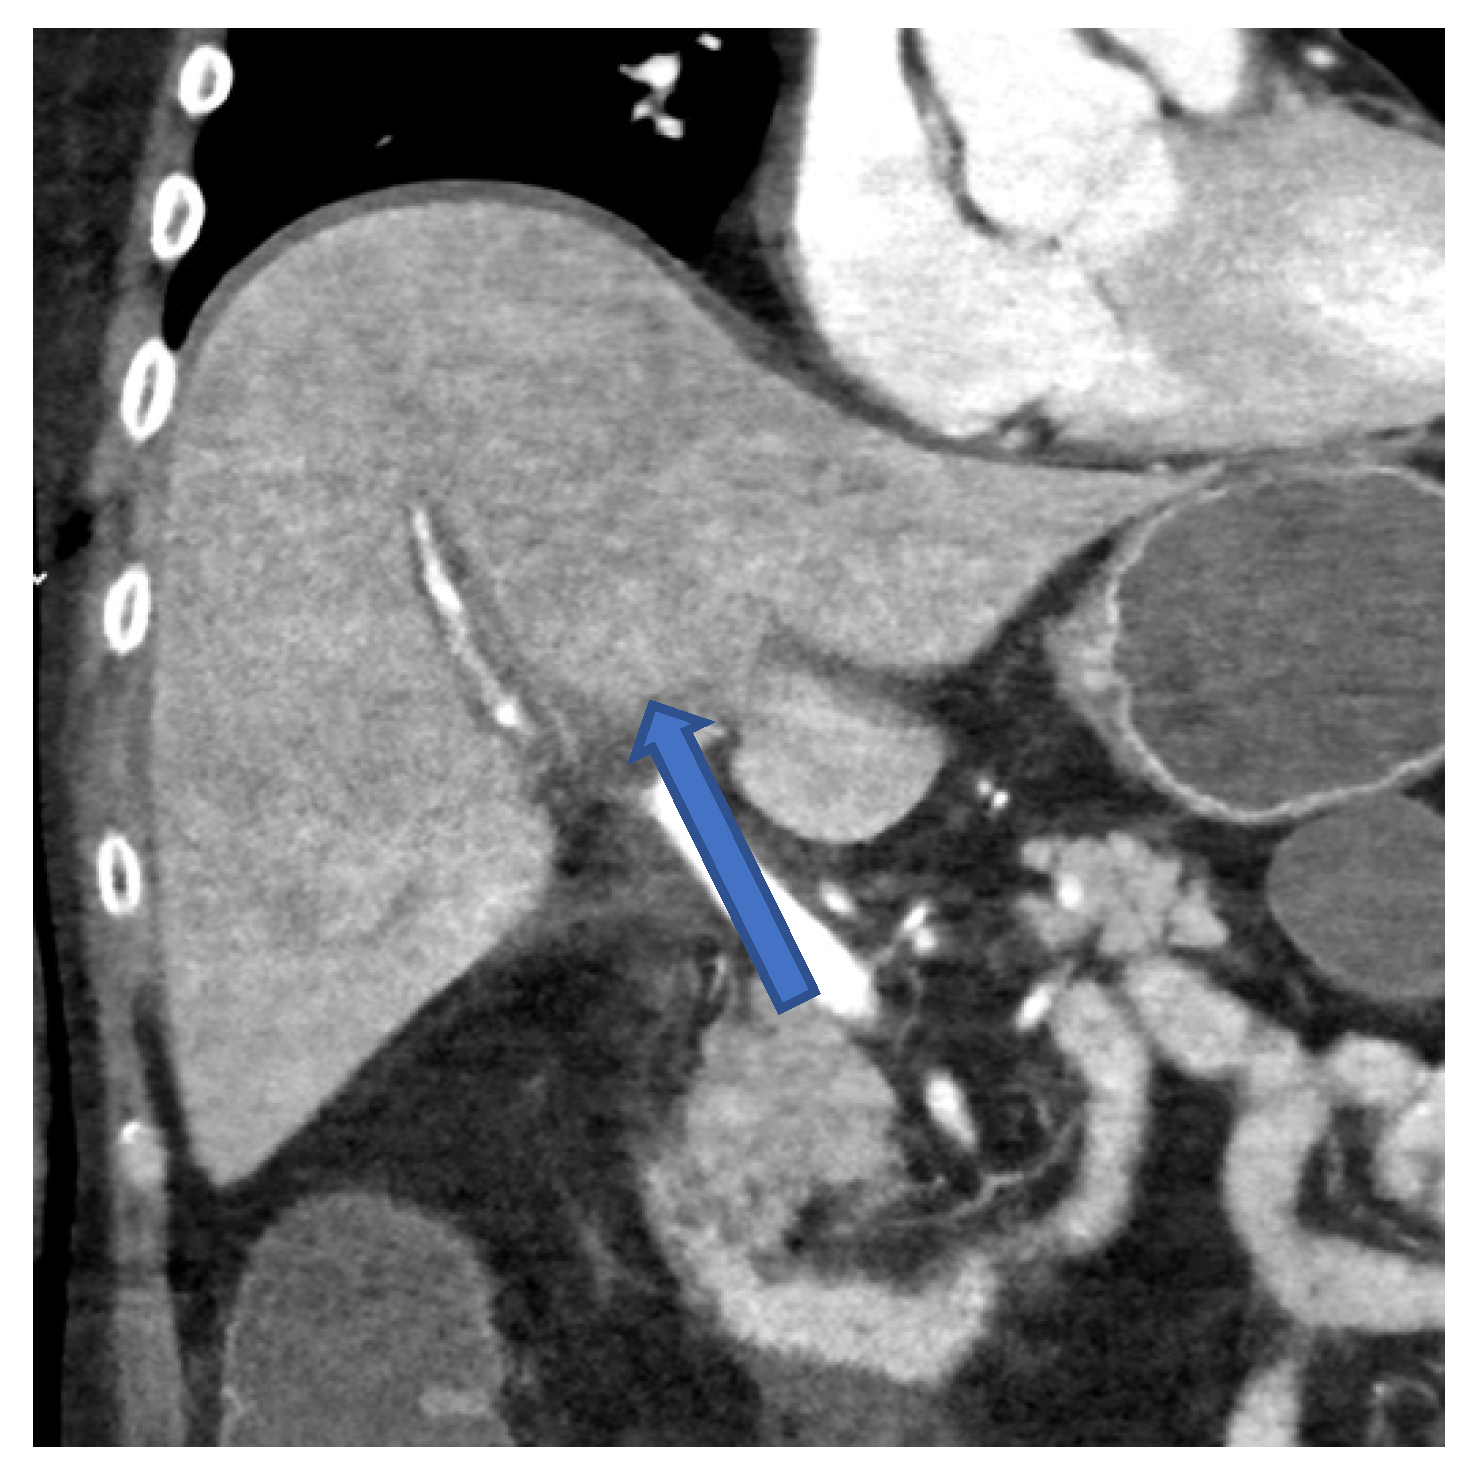

Figure 3.

CT scan of the abdomen in frontal plane of case 1 showing an irregular contrasted liver parenchyma 2 days before the patient died.

Transjugular biopsy of the liver revealed multifocal hepatocellular necrosis and a lobular chronic inflammation consistent with a viral hepatitis (Figure 2a). Histopathologically, a GvHD, as well as cytomegalovirus (CMV) and EBV infection, could be excluded. A CT scan presented an irregular contrasted parenchyma, a hepatic edema, and a dilatated common bile duct (Figure 3). Treatment with 325 mg of cidofovir and immunoglobulins was applied immediately after HAdV was diagnosed. The coagulation dysfunction was aggravated with recurrent bleeding complications. In addition, a central pulmonary embolism deteriorated the respiratory situation with development of treatment-resistant lactic acidosis caused by ALF. The patient died only 4 days after symptom onset due to fulminant multiorgan failure in disseminated HAdV infection.

A PCR of the blood is considered the gold standard for diagnosing a HAdV viremia [5]. In addition to PCR, diagnosis of hepatitis with subsequent ALF can be confirmed by CT scan (Figure 3) and by liver biopsy (Figure 2), as shown in cases 2 and 3.